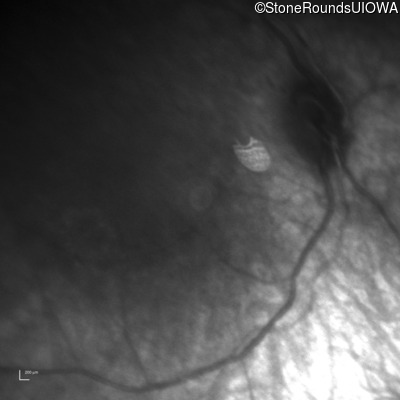

Infrared Fundus Photograph - Right -

No Light Perception

Infrared Fundus Photograph - Left -

Light Perception